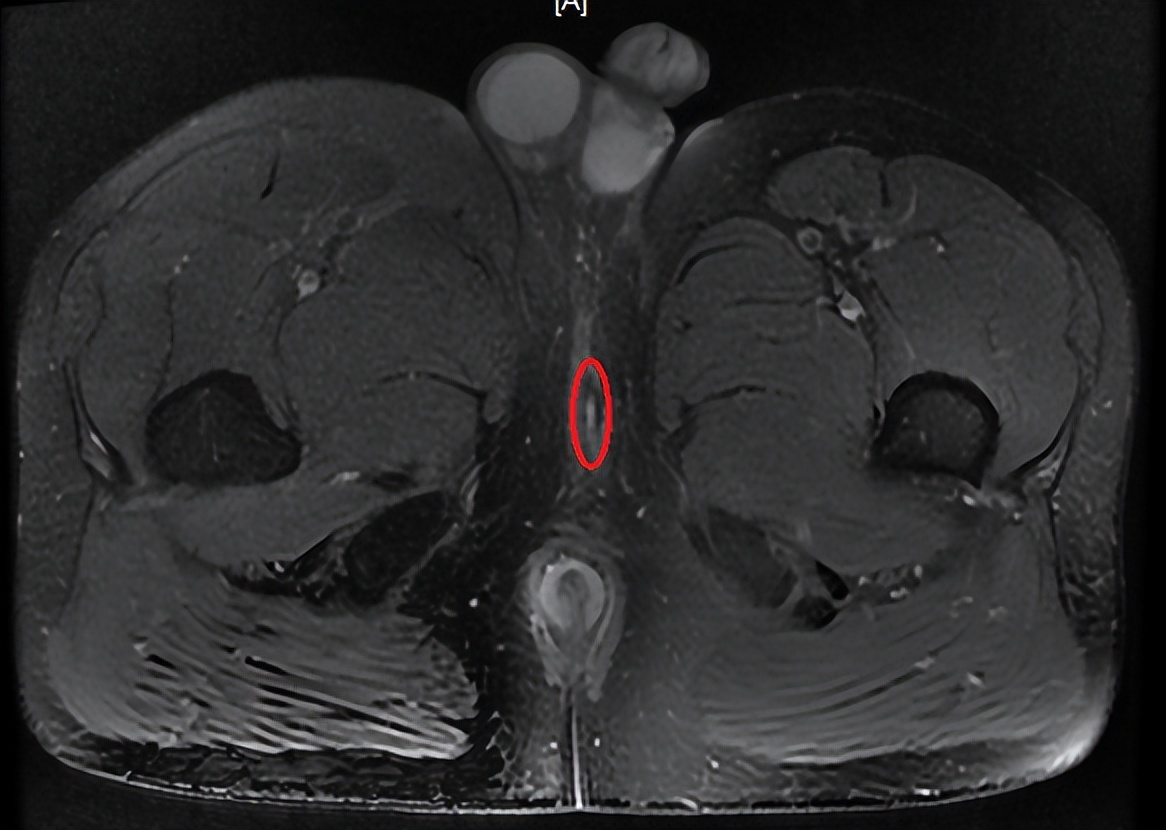

盆腔MRI

术前、术后(图略)。

患者看完术后的图片,露出恍然大悟的表情,呀,原来我手术的伤口这么大啊,怪不得别人两天就不疼了,我到现在还不敢坐,一坐就疼。